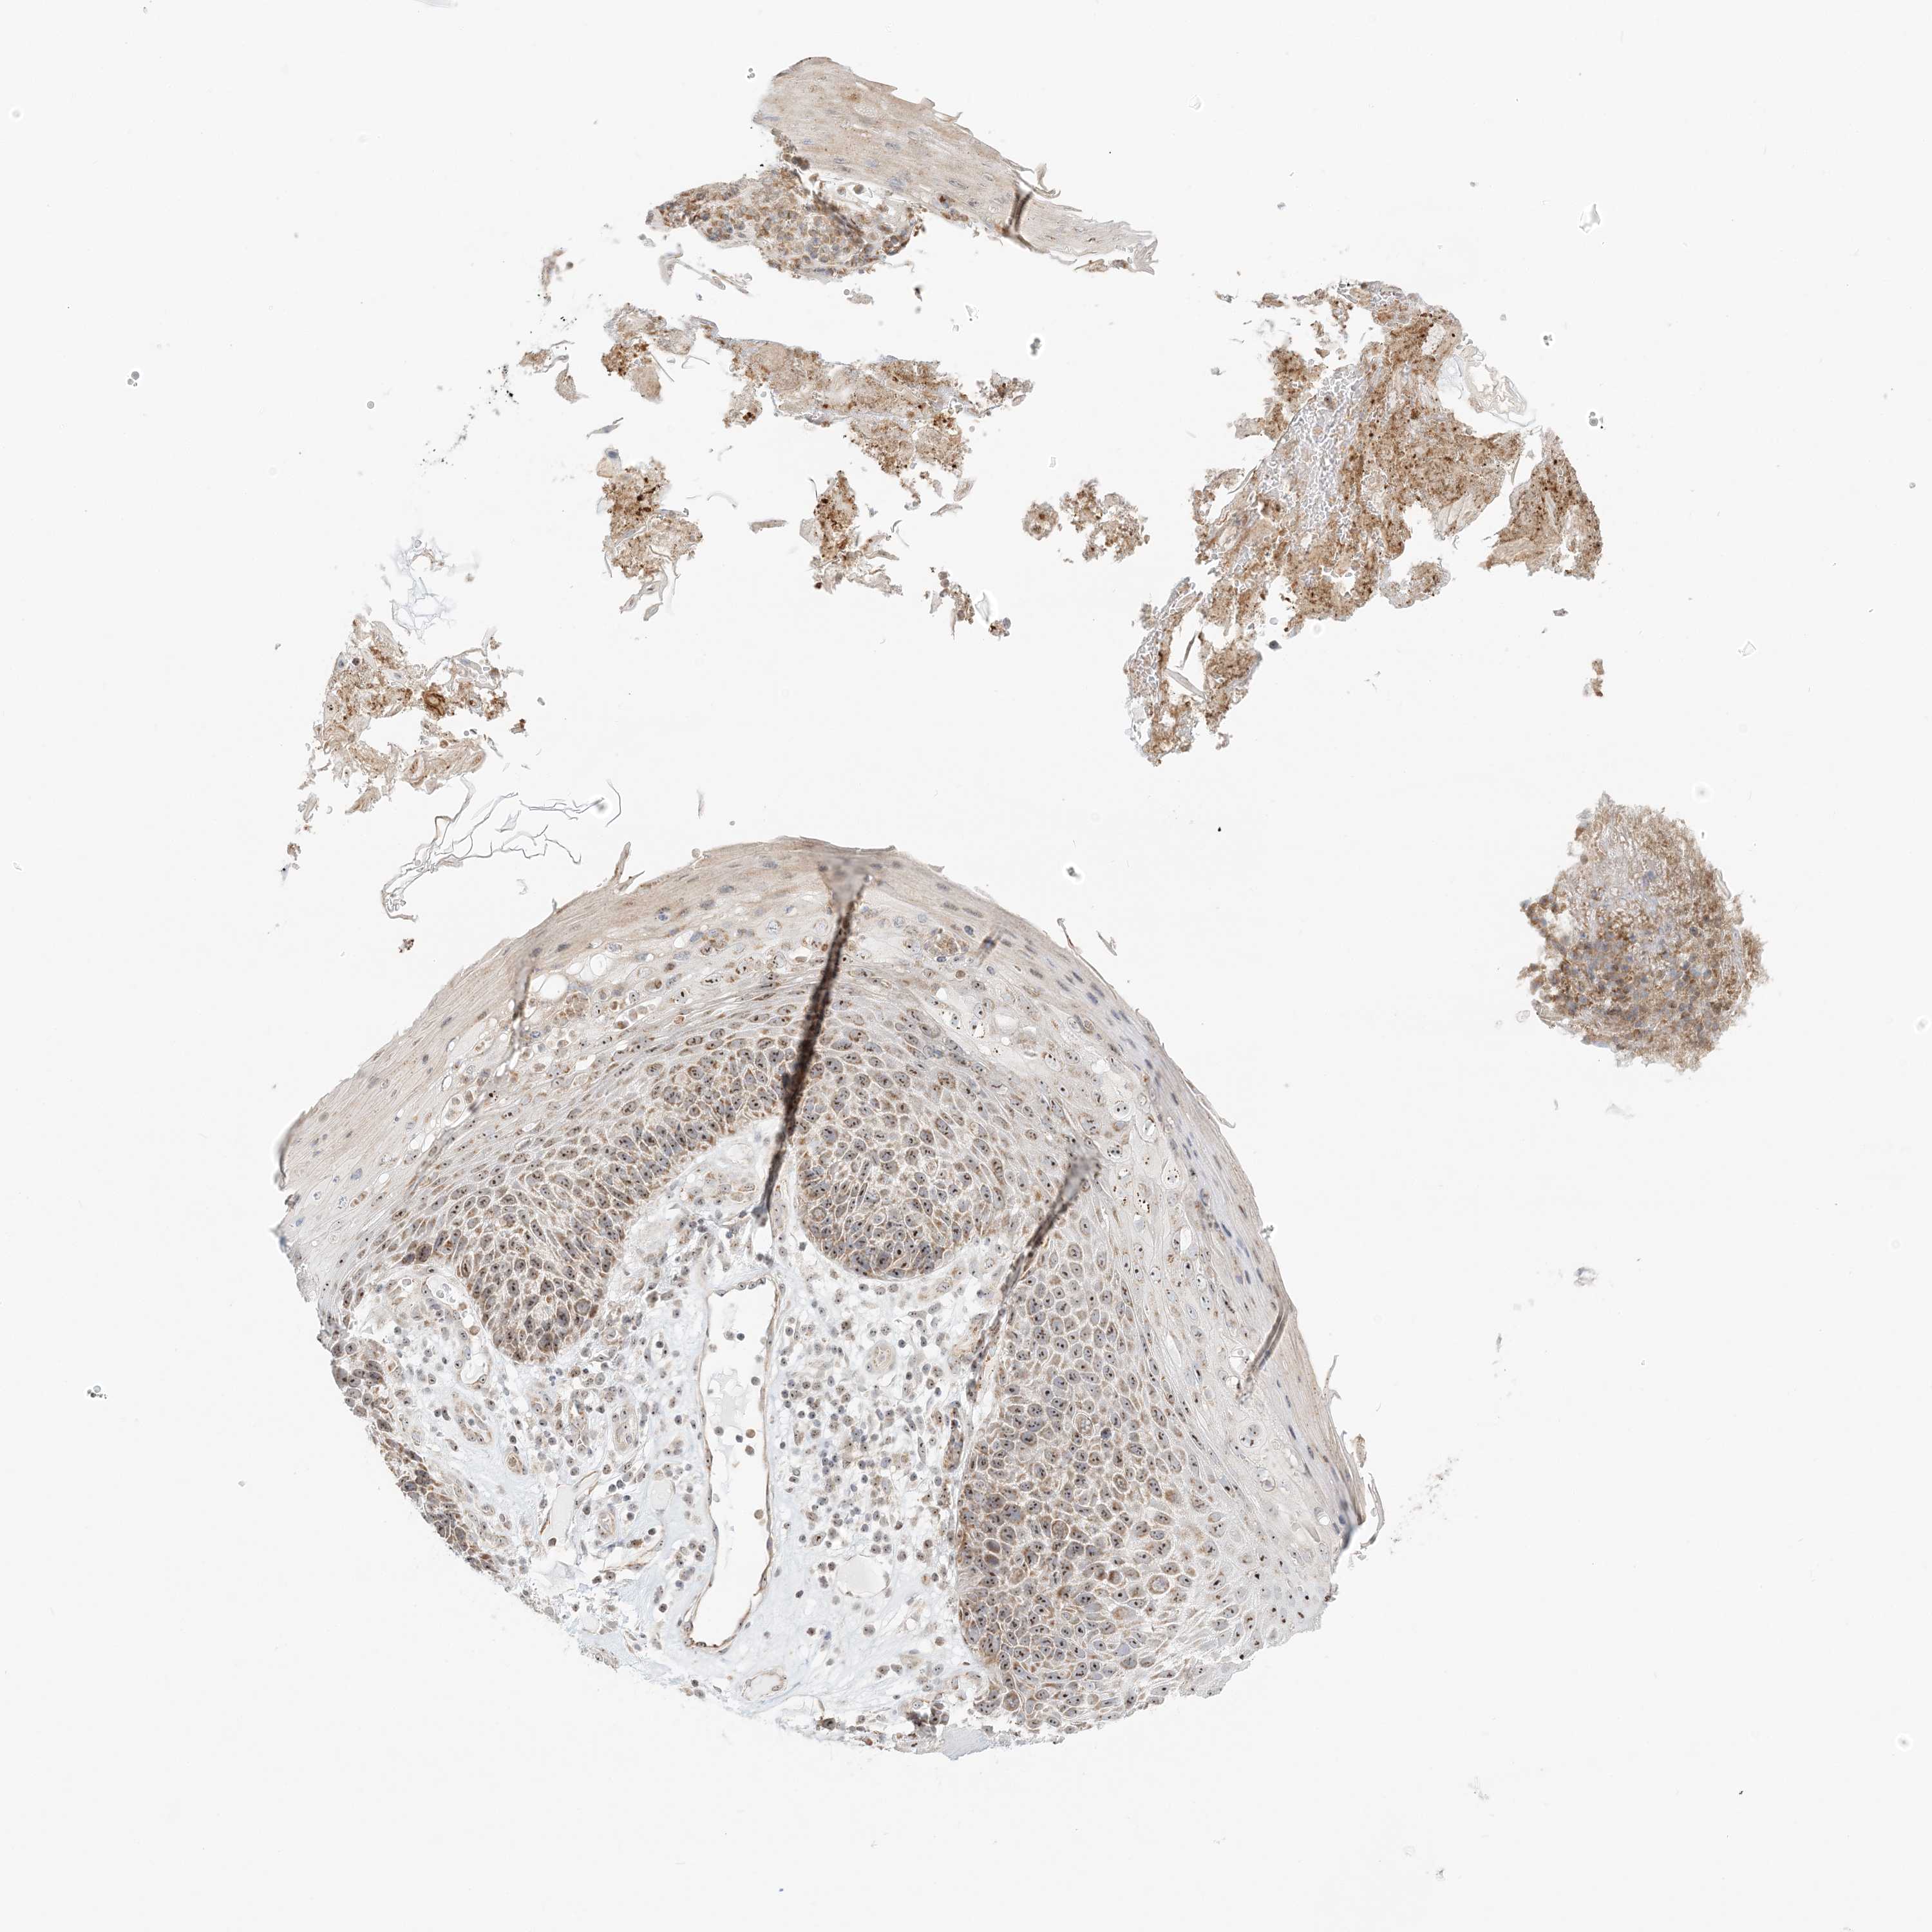

Basal cell and squamous cell cancer

SKIN CANCER - Protein expressioni

A mouse-over function shows sample information and annotation data. Click on an image to view it in a full screen mode. Samples can be filtered based on level of antibody staining by selecting one or several of the following categories: high, medium, low and not detected. The assay and annotation is described here.

Antibody stainingi

Antibody staining in the annotated cell types in the current human tissue is reported as not detected, low, medium, or high, based on conventional immunohistochemistry profiling in selected tissues. This score is based on the combination of the staining intensity and fraction of stained cells.

Each image is clickable and will lead to virtual microscopy that enables deeper exploration of all samples and also displays staining intensity scores, fraction scores and subcellular localization as well as patient and tissue information for each sample.

Antibody HPA037444

Staining

Medium

Intensity

Moderate

Quantity

75%-25%

Location

Nuclear

Squamous cell carcinoma, NOS

Squamous cell carcinoma, metastatic, NOS